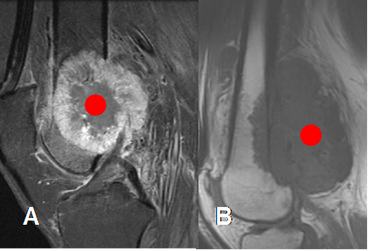

Fig 43. Masa de tejidos blandos.

A y B: RM sagital. Masas de tejidos blandos en el fémur distal. En A el centro geométrico se localiza en el hueso, indicando origen óseo y en B, el centro esta por fuera del hueso, lo que sugiere origen en los tejidos blandos.